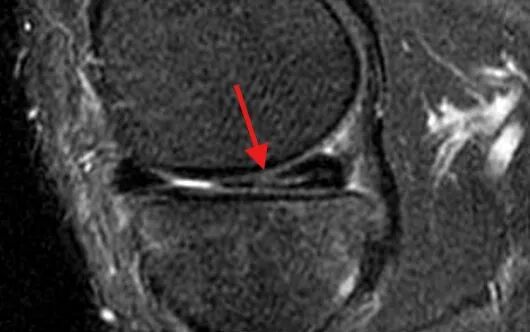

对于怀疑半月板损伤患者,应进行膝关节核磁共振(MRI)检查,该检查无创、分辨率高,对半月板损伤有很高的敏感性和特异性。根据半月板损伤的MRI表现,可以分成3级:

0 级

为正常的半月板,呈均匀的低信号,半月板形态规则。

I 级

表现为不与关节面相接触的灶性椭圆形或球形高信号。

II 级

表现为水平、线性半月板内高信号,可延伸至半月板的关节囊缘,但未达到半月板的关节面。

III 级

半月板内高信号达到上或下关节面。

I级、II级损伤通常为退变信号,不需要医学干预。III级损伤显示高信号贯通到半月板表面了,等同撕裂,一般伴随症状,需要医学干预。